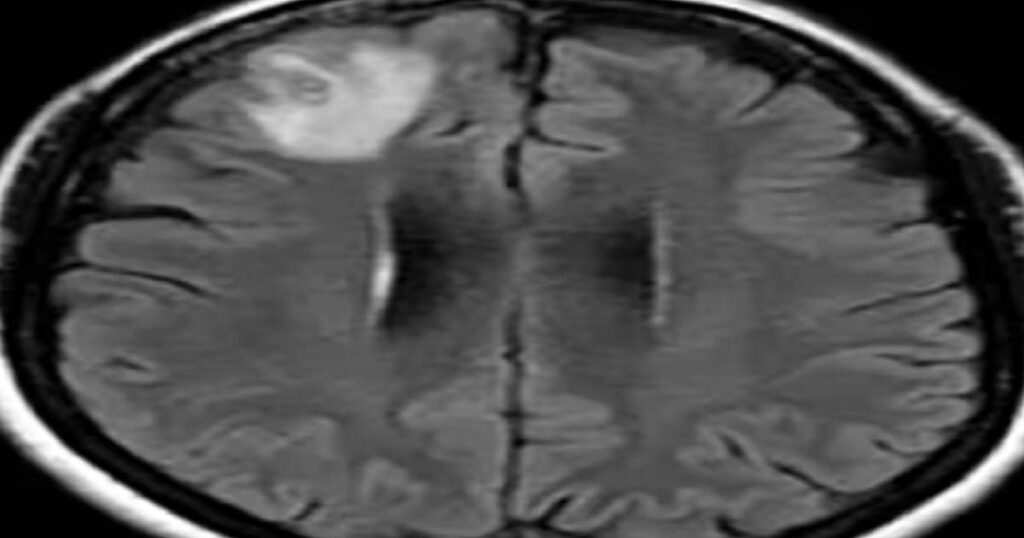

År 2022 inkluderade hennes symtom också glömska och depression, vilket ledde till en remiss till Canberras sjukhus. En MR-undersökning av hennes hjärna avslöjade abnormiteter som krävde operation.